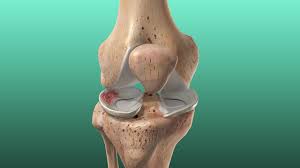

A torn meniscus does not mean you will need surgery. Mri and knee arthroscopy how do doctors diagnose a meniscus tear? You may only remember feeling pain after you got up from a squatting position, for example. Sometimes, the knee will lock, making it impossible to fully extend or bend the leg. What causes a torn meniscus? How does one know if they have a torn meniscus? Usually, a torn meniscus doesn't require this, but there are situations where it can. The meniscus sits between the cartilage surfaces of the bone to distribute weight and to improve the stability of the joint.

The meniscus sits between the cartilage surfaces of the bone to distribute weight and to improve the stability of the joint. In your case it a torn meniscus is bad news so you should rest for a while. A torn meniscus is one of the most common knee injuries we treat. Pain and swelling are common symptoms of a torn meniscus. The pain may be felt along the joint line where the meniscus is located or may be more vague and involve the whole knee. A torn meniscus does not mean you will need surgery. How does one know if they have a torn meniscus? Where do you feel the pain from a torn meniscus?